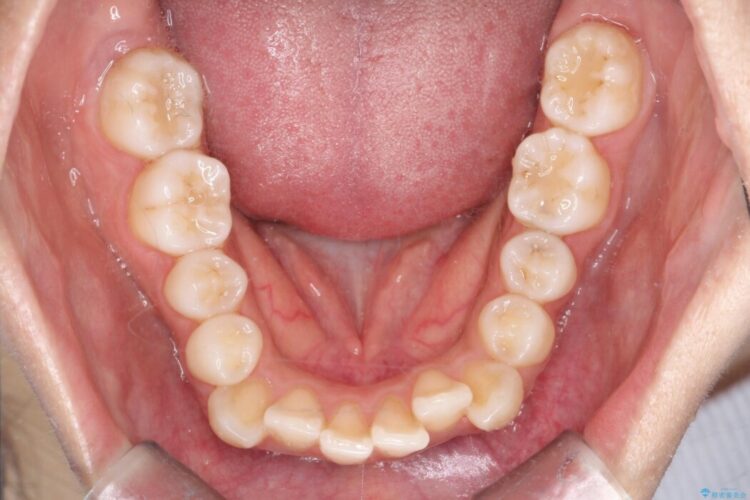

前歯のガタつきと、口元の突出感を改善したいと来院されました。

矯正検査の結果、歯を並べるスペースが不足しており、そのまま並べてしまうとさらに突出感が目立つ恐れがありました。

そのため上下左右4番を抜歯し、ガタつきを改善しながら前歯をしっかりと後方へ下げ、口元のボリュームを抑えていく計画を立案しました。

複雑に重なり合っていた前歯を、抜歯で作ったスペースを活用して丁寧に整列。単に並べるだけでなく、角度を1ミリ単位で調整しながら後ろへ下げることで、口元の突出感をスッキリ解消しました。